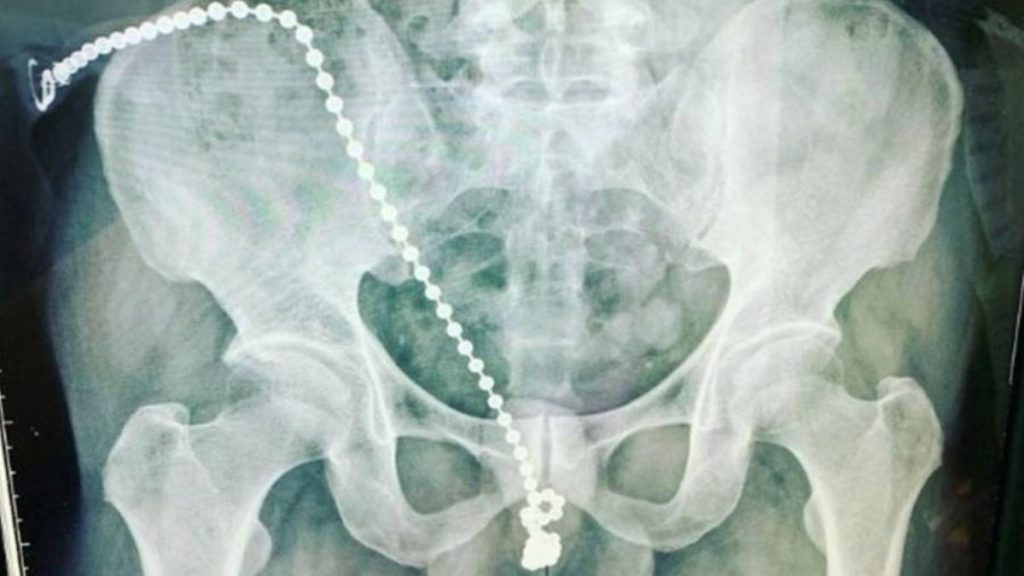

Um homem foi levado às pressas para um hospital de Taipé, em Taiwan, após sentir fortes dores no pênis. Médicos descobriram que o paciente, na casa dos 30 anos, tentou “atingir o orgasmo” introduzindo uma corrente com bolinhas de metal na uretra.

Reclamando muito das dores, que ele descreveu como “choques elétricos”, teve que passar por um procedimento cirúrgico de emergência, para retirada da corrente de metal. O homem também não conseguia ir ao banheiro.

Em entrevista coletiva, o urologista Gao Weichang, que tratou o paciente, disse que ele não sabia como remover a corrente de bolinhas, de tamanho considerável, que estava embutida dentro de seu pênis, por medo de se machucar ainda mais.

“O paciente não sabia como remover a corrente em casa. Ele já estava ferido e a corrente, presa. Mas se ele tentasse retirá-la, toda a sua uretra poderia ter sido danificada”, destacou.

O médico acrescentou que, em circunstâncias normais, a corrente deveria ter deslizado para fora, mas a uretra do homem estava apertada devido à tensão.

Weichang disse que o homem estava sentindo um “severo desconforto” e as bolinhas estavam afetando os nervos sensíveis do seu órgão genital, causando uma “dor aguda como choques elétricos”.

Os cirurgiões tiveram que “abrir” seu pênis para desatar o nó que se formou na corrente antes de reconstruir sua uretra em um procedimento complicado, mas bem-sucedido.